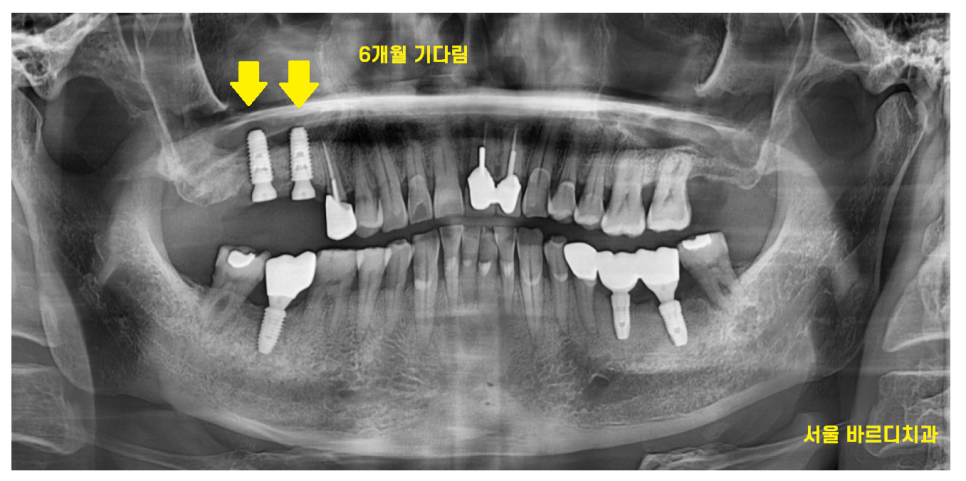

24.01.04

상일동역 임플란트 수술 이후

6개월정도 기다렸습니다.

24.01.23

상일동역 임플란트의 원인이

치아 솟음이기에

잇몸뼈가 단단해질때까지

기다리고 기다렸습니다.